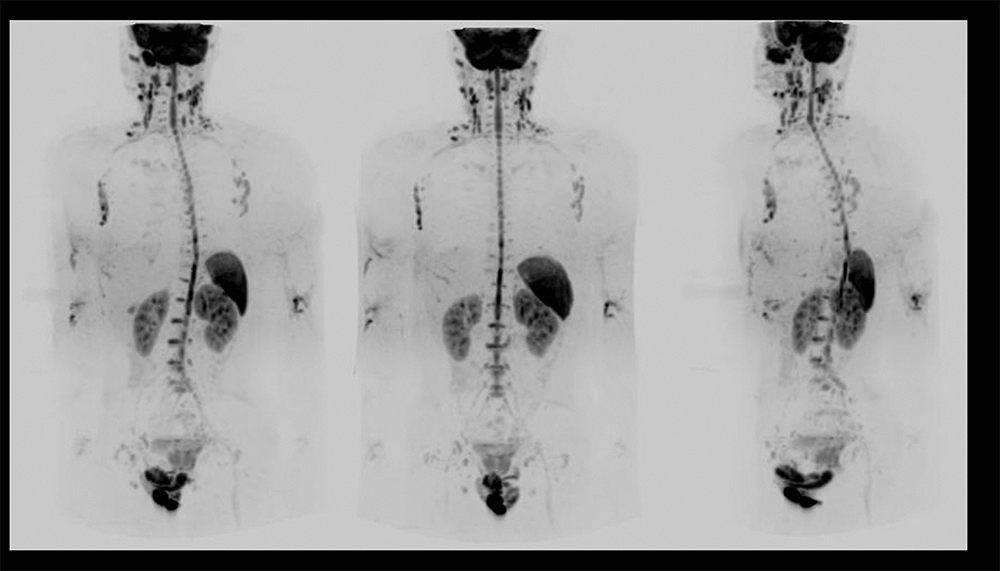

Case3 呼吸器内科:肺癌の骨転移検索目的

70代、男性。肺癌に対して放射線化学療法後、腰痛出現するも単純CTでは原因を特定できず、WBDWIを施行した。WBDWI MIP(①)では、頸椎、胸椎、腰椎、鎖骨、骨盤骨、大腿骨など多発骨転移と肝転移も認められる。②~④の矢状断像では、WBDWI MIP(①)で椎体に重なっていた棘突起の転移、CT(⑤⑨)では描出困難な腰椎、仙骨、腸骨転移(➞)がMRI(⑦⑩)では明瞭に描出されている。まさに骨梁間型骨転移の典型例である。単純CTでは描出されていない肝転移(➞)においてもDWI(⑦)、T2WI(⑧)では明瞭に描出されている(図12)。依頼医からは肺癌は骨梁間型骨転移が多く認められるため、肺癌の骨転移検索にWBDWIは非常に有用であると評価が得られた。

Architect_Okazakishimin02_15.png図12 肺癌の骨転移検索目的